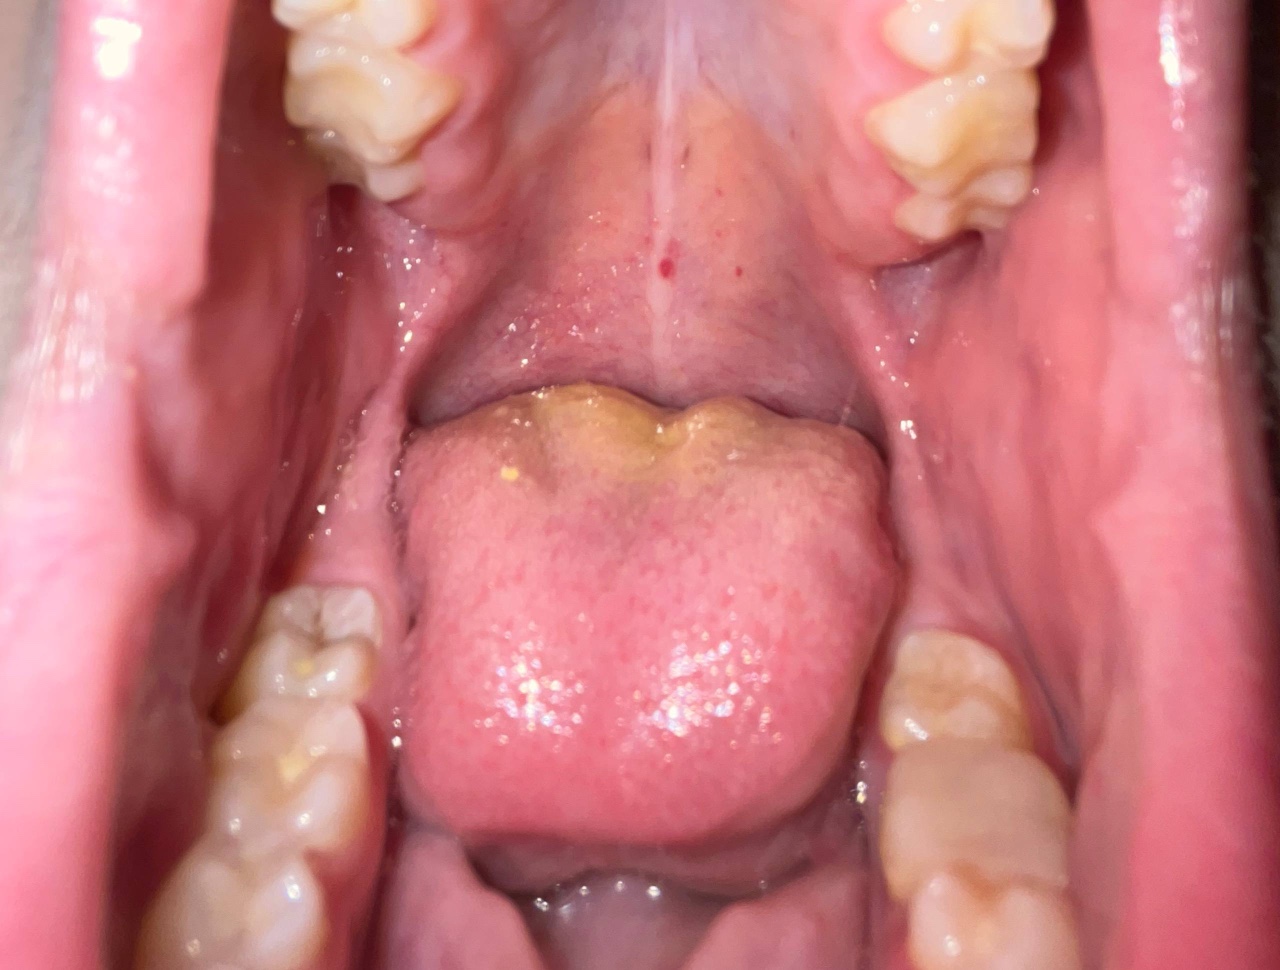

Красные пятна во рту возможно аллергические

Здравствуйте, столкнулся с проблемой, красные пятна во рту, Незнаю причину их появления раньше такого не замечалось, возможно повлияло появление собаки в доме, других причин не предполагаю, в интернете ответа нету